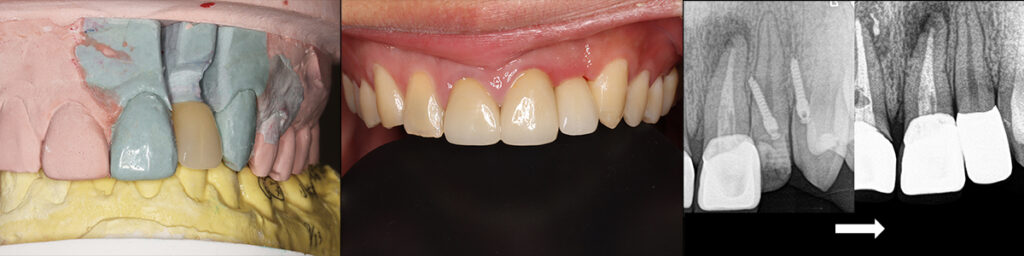

CT撮影により歯根の近接具合の確認とアンカースクリューの設置位置の確認

アンカースクリューによる圧下矯正と歯冠を歯肉下までスライスして前方傾斜移動

支台歯(修復前の形成歯)が対合前歯の前方に位置したら仮歯を装着し矯正は完了

最終修復物(ジルコニアセラミック冠)と修復後画像 右はアンカースクリューと術後X線写真